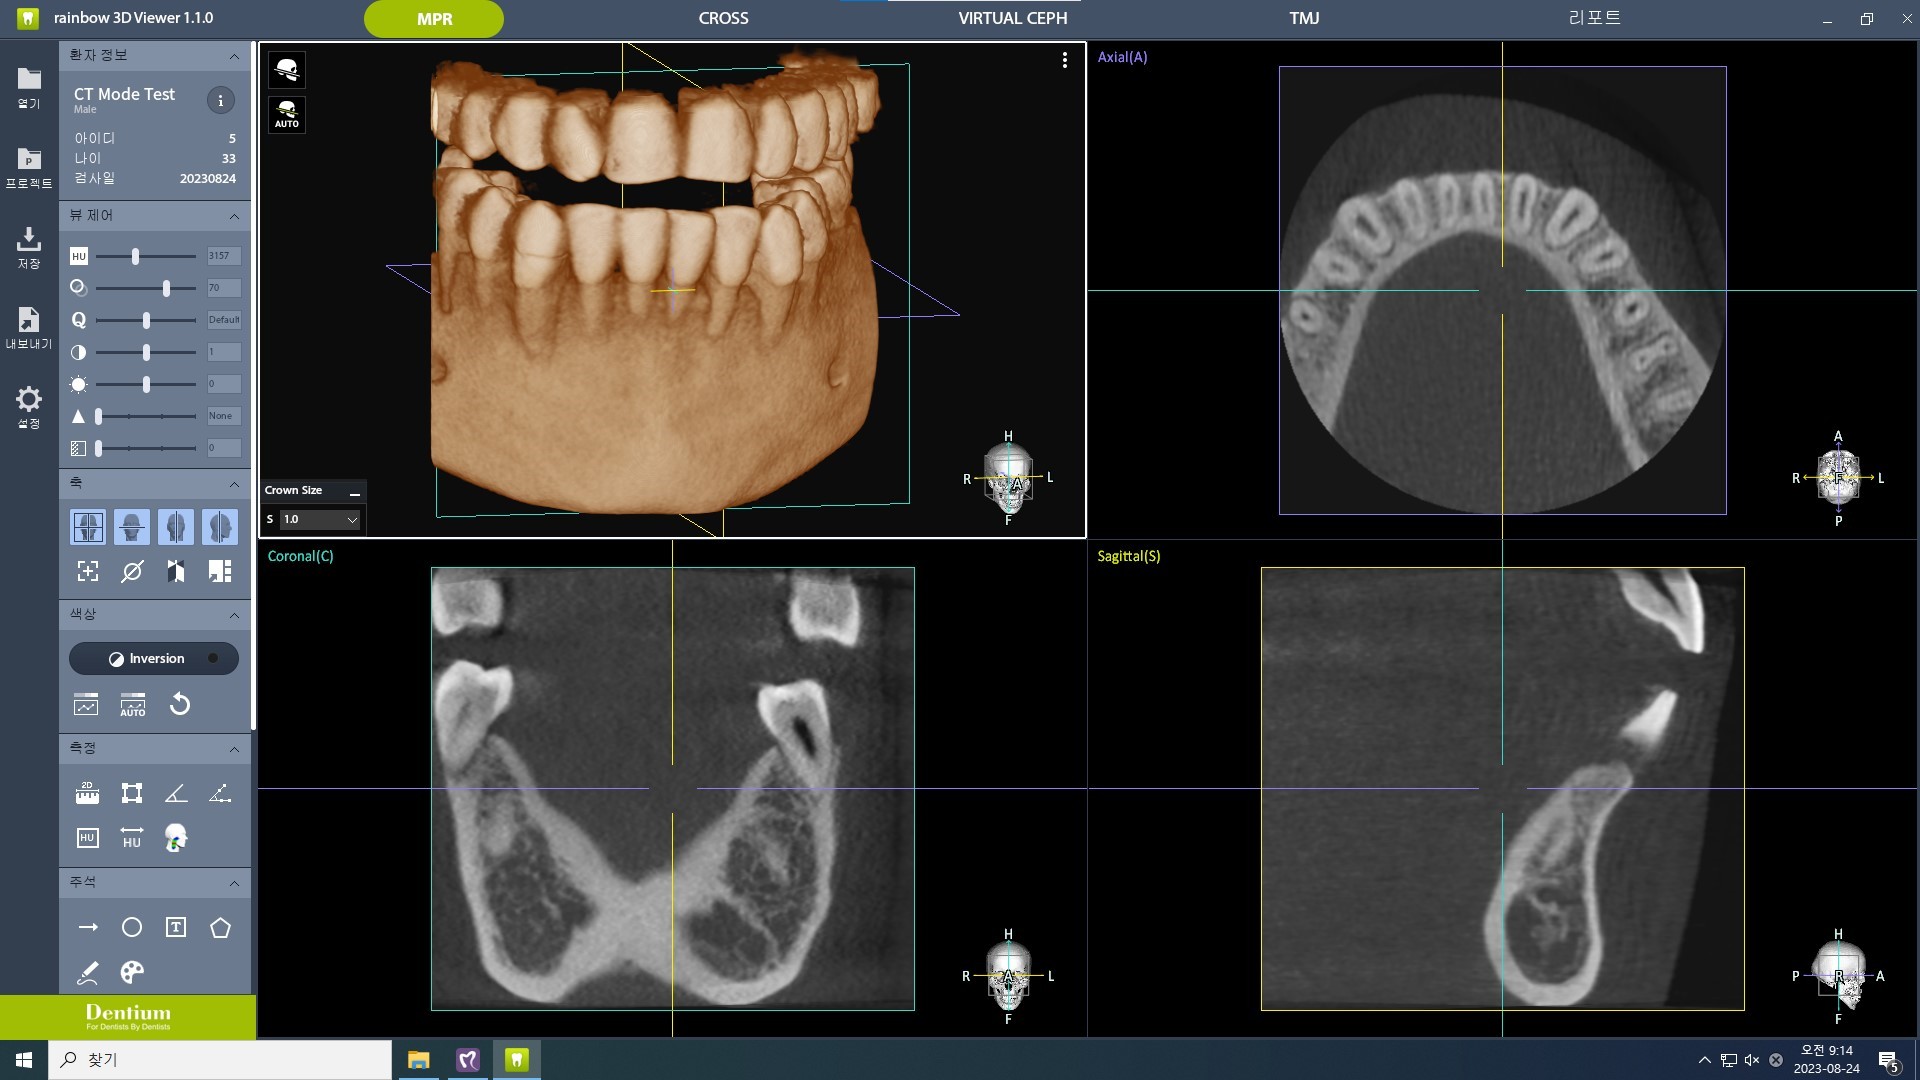

Planificarea implantului asistată de Inteligență Artificială (AI)

Rainbow™ CT integrează funcții avansate de Inteligență Artificială pentru a automatiza și simplifica sarcinile de rutină. De la identificarea poziției dinților lipsă până la stabilirea poziției inițiale a implantului și coroanei, AI-ul Dentium asigură o planificare eficientă și precisă a tratamentelor.

Implant/Coroană: Inteligența Artificială Dentium detectează automat poziția dinților lipsă și stabilește poziția inițială a implantului și coroanei pentru a simplifica planificarea implantului.

Arcada: Algoritmul AI generează automat linia arcadei în doar câteva secunde, cu o precizie ridicată.